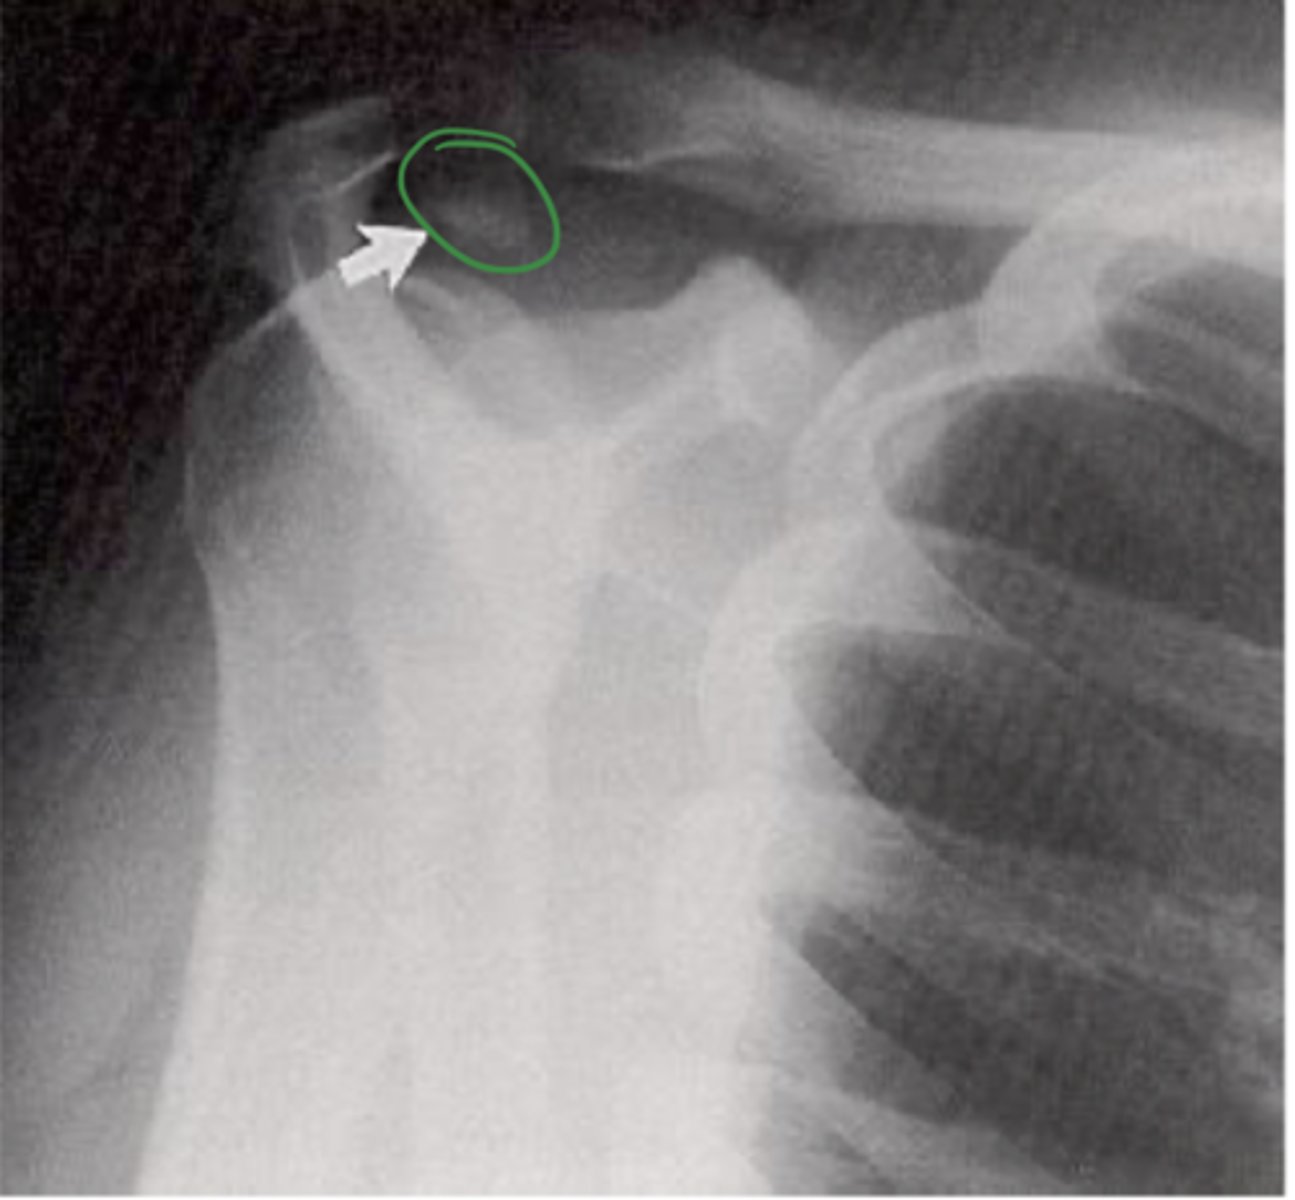

AP of the right shoulder

What view does this show?

Bankart fracture

What is the issue?